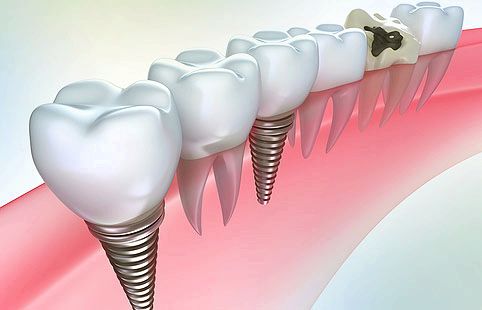

Імплантант зуба: сутність і-

Карієс між зубами вимагає акуратного і дбайливого лікування, так як від цього буде залежати стан зуба, а також естетичне сприйняття.

Будь-яке лікування зуба проходить під місцевою анестезією. так як процес цей досить болючий, особливо коли справа стосується передніх зубів, або ж інфекції поширилася до зубного нерва.

Перед стоматологом стоїть певна задача - дістатися до пошкодженого місця з мінімальними втратами. Карієс між зубами підступний тим, що, щоб дістатися до нього, необхідно просвердлити здорову частину зуба. Після того, як потрібне місце виявлено, у стоматолога стоїть два завдання:

- Відновити жувальну поверхню

- Відновити контакт зуба з іншими зубами. Це потрібно зробити для того, щоб в майбутньому в проміжок не потрапляв їжа, яка буде гнити, і карієс